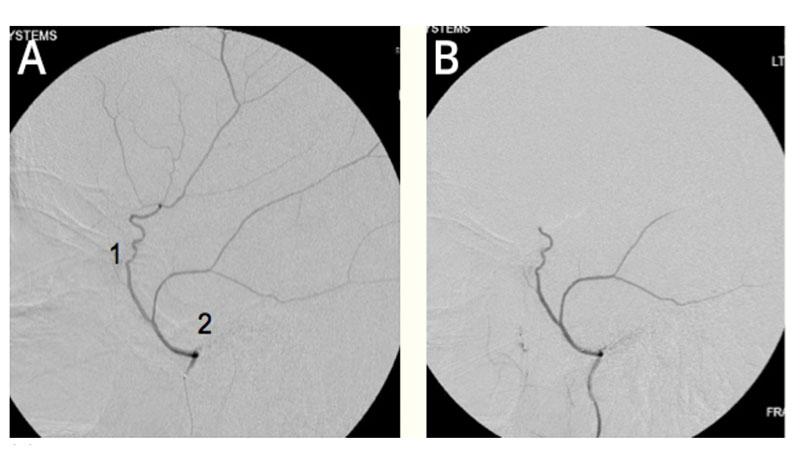

(A) Common configuration of the middle meningeal artery with a common trunk that divides into frontoparietal (1) and squamosal/temporal (2) branches. (B) With this configuration, embolization can be performed with the microcatheter tip proximal to the bifurcation of these branches to achieve safe embolization of the maximal amount of dura.